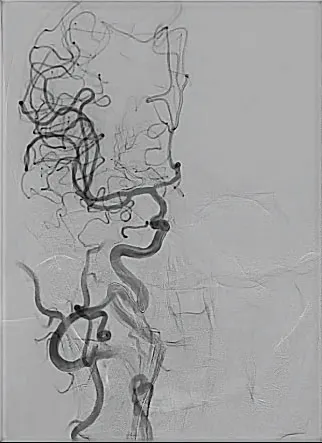

PROCEDURE

An 8-F right common femoral artery access was achieved, and the patient was systemically anticoagulated with heparin. A Bobby™ balloon guide catheter (BGC) (Terumo Neuro) was navigated over a 5-F Simmons Select catheter (Penumbra, Inc.) and a 0.035-inch Glidewire Advantage® guidewire (Terumo Interventional Systems) into the left CCA. Biplane cervical and cranial angiograms were then obtained. A 99% stenosis was present in the proximal left cervical ICA, with delayed filling of the intracranial vasculature and no evidence of occlusion (Figure 2A and 2B).

Figure 2. Prestent anteroposterior and lateral angiograms demonstrating near-complete occlusion of the proximal left cervical ICA (A, B). Inflated balloon across the stenotic lesion with BGC inflated for flow reversal and proximal protection (C). Anteroposterior and lateral angiograms after stent placement with significant improvement in caliber and flow (D, E).

An 8- X 25-mm Roadsaver stent was then navigated across the stenotic region and deployed. Intermittent angiography was performed, demonstrating satisfactory stent deployment (Figure 2D and 2E). The NAV6 was then retrieved with a total filter time of 5 minutes. Final biplane cervical and cranial angiography was performed and showed brisk flow through the stent, with significant improvement in intracranial filling (Figure 3).

Figure 3. Prestent cranial angiogram showing sluggish and delayed intracranial flow (A). Poststent cranial angiogram demonstrating intracranial flow and significant improvement, with full opacification of the ACA and MCA and their arborizations (B).